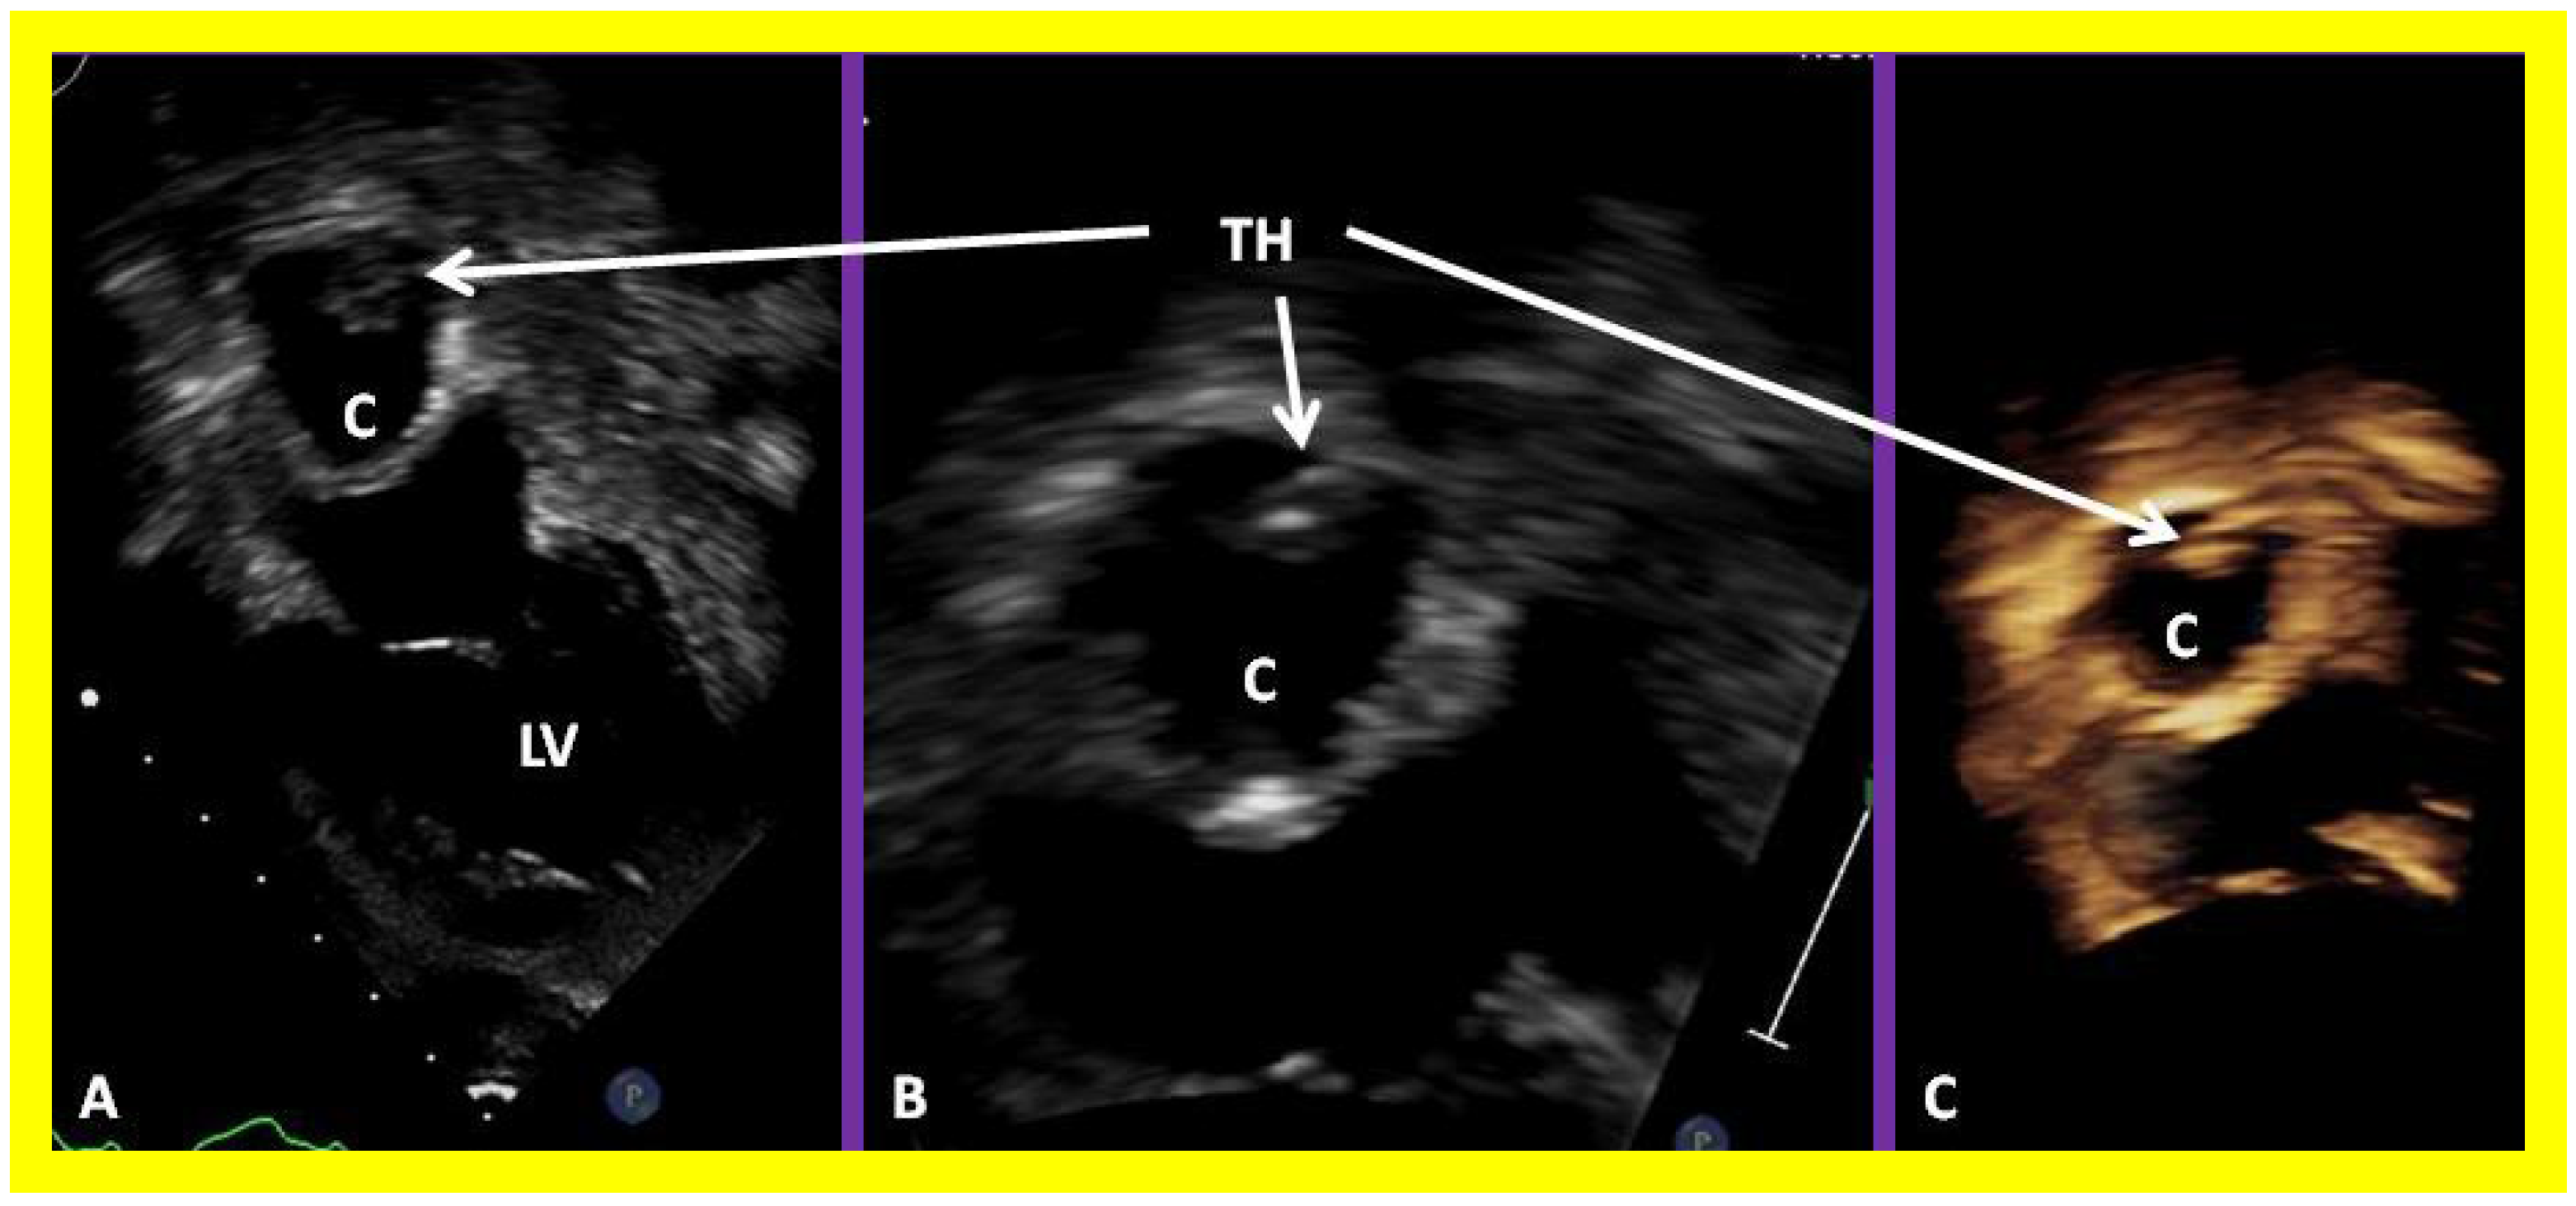

Figure 13. Two dimensional echocardiographic video frames demonstrating (a) an atretic tricuspid valve (ATV) between the right atrium (RA) and right ventricle (RV), (b) a large subtruncal ventricular septal defect (VSD), (c) thickened and somewhat domed truncal valve (TV) leaflets, and (d) the origin of the pulmonary artery (PA) from the posterior aspect of the truncus arteriosus (TA). LA, left atrium; LV, left ventricle. Reproduced from Rao PS, et al. Am Heart J 1991;122:829–835 [31].

Applsci 11 09472 g013

Figure 14. Video frames from a two dimensional echocardiographic and color Doppler study demonstrating (a) an atretic tricuspid valve (ATV) between the right atrium (RA) and right ventricle (RV), and blood flow from the left atrium (LA) into the left ventricle (LV) across the mitral valve. The RV (arrow) is very small and hypoplastic. (b) LV and RV with a large ventricular septal defect (VSD) below the truncus arteriosus (TA). Turbulent flow across the truncal valve suggests truncal valve stenosis. (c) The origin of the pulmonary artery (PA) from the TA by color flow (arrow), and (d) the division into right (RPA) and left (LPA) pulmonary arteries from the PA in a short-axis view. TV, truncal valve leaflets. Reproduced from Rao PS, et al. Am Heart J 1991;122:829–835 [31].

Applsci 11 09472 g014

The relationship of the great arteries is examined next in order to classify them into various types, as mentioned above. The relationship of the great arteries (Figure 2, top) is established by following the vessels arising from the ventricles until the pulmonary artery (PA) bifurcation or aortic arch. In Type I patients with normally related great arteries, the aorta arises from the LV (Figure 10) and in Type II patients with transposition of the great arteries, the PA arises from the LV (Figure 11; Figure 12). In Type II patients, the blood vessel arising from the LV should be traced to demonstrate its branching into the right and left PAs (Figure 11; Figure 12). In Type III patients, it may be a little more difficult to assign the great artery relationship and, sometimes, other imaging studies, including angiography, may be needed to define the great artery relationship. In Type IV with truncus arteriosus, the limited data suggest that this can be performed by echocardiography (Figure 13; Figure 15). In the example shown [31], the atretic tricuspid valve (Figure 13a and Figure 14a), VSD (Figure 13b and Figure 14b), hypoplastic RV (Figure 14a), single vessel (truncus) arising from the heart (Figure 13c,d, and Figure 14c,d), and origin of the PA and its division into branch PAs (Figure 13d, and Figure 14c,d) were demonstrated.